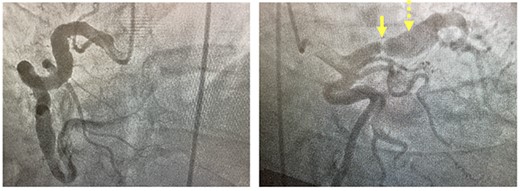

Coronary angiogram. Left panel: injection of fusiform aneurysm of right coronary artery. Right panel: coronary angiogram injection of the left-sided coronary circulation with solid yellow arrow pointing to tight left anterior descending stenosis and dotted yellow arrow pointing to post-stenotic aneurysm.

His initial troponin was not elevated although the electrocardiogram showed new ST depressions in the medial precordial leads and subsequent troponins were elevated. He was transferred to our institution and underwent left heart catheterization which demonstrated a right dominant circulation with ectasia of the right coronary artery, a fusiform aneurysm of the left anterior descending coronary artery (LAD) and a generous-sized left circumflex coronary artery (Fig. 1). There was a 99% stenosis of the LAD with post-stenotic dilatation up to 13 mm with gradual normalization over the course of the remainder of the vessel. An echocardiogram showed a left ventricular ejection fraction of 35% without valvular pathology. Percutaneous coronary intervention (PCI) was thought to be a poor option because the distal portion of the stent would not oppose the wall of the vessel but be ‘floating’ in the aneurysmal portion of the artery pre-disposing thrombus formation. Therefore, in anticipation of operative intervention, a computed tomography scan was done to further define the anatomy. The scan demonstrated extensive wall thickening and contour irregularity suggestive of diffuse coronary arteritis (Fig. 2). The study also showed a dilated main pulmonary artery up to 46 mm and an aberrant right subclavian artery coming off the distal aortic arch and passing behind the esophagus.